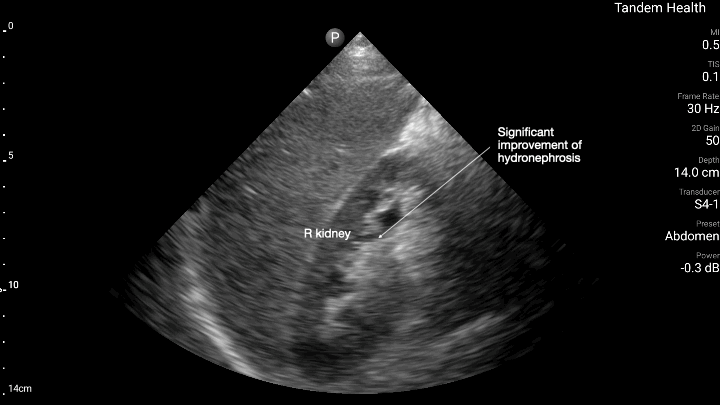

It is all too common to see patients come into the hospital due to end results of these preventable conditions, such as stroke, heart attack, heart failure, kidney disease, etc. Often, there was some kind of barrier preventing patients from following up consistently with a primary care physician, whether due to lack of insurance, prior poor experience/communication with healthcare teams, fear of surprise bills/high copays, etc.